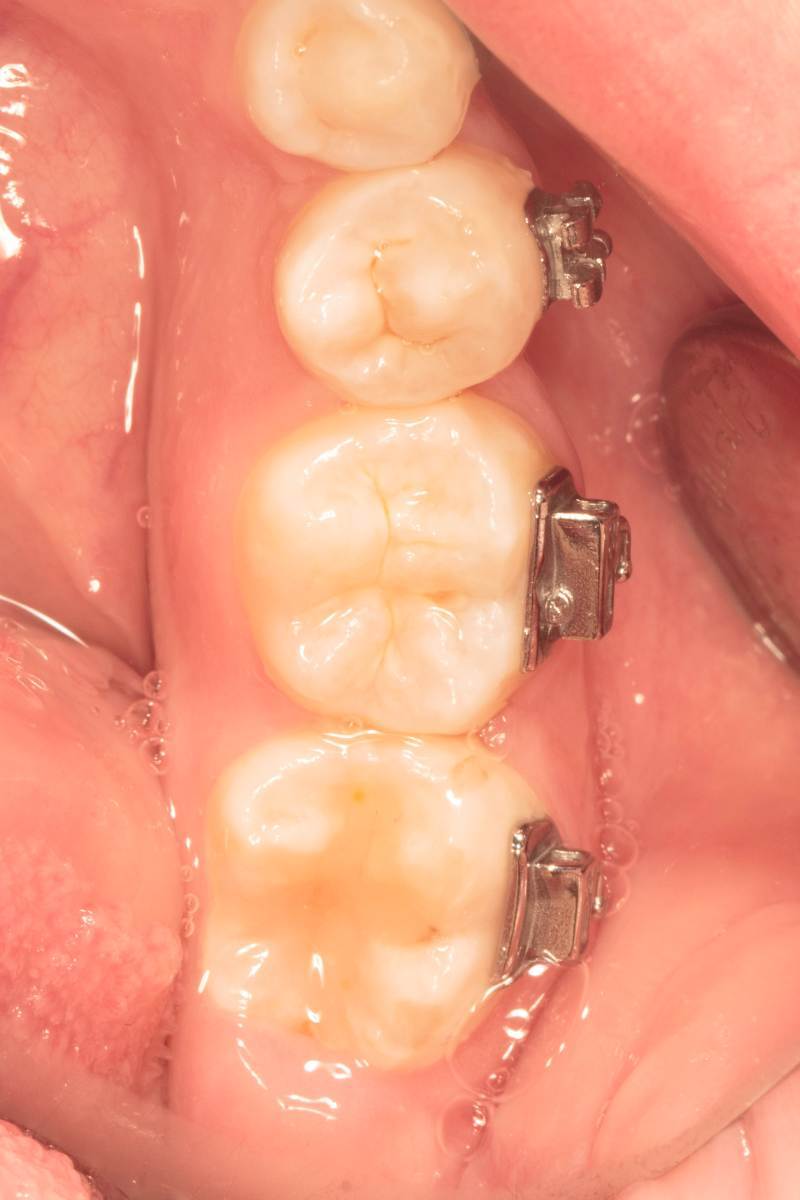

Женька Опубликовано 28 ноября, 2025 Поделиться Опубликовано 28 ноября, 2025 Всем привет, коллеги! 14 лет, терапевты ставят трещину по КТ (снимков до, к сожалению нет, косяк, каюсь). чуть сепарировав зуб и глянув на зуб под отлетевшим куском пломбы трещина "подтвердилась". Кейс на фото. Из интересного - маленький реколл в 1.5 года и спокойное перемещение зуба брекетами! 4 1 2 Ссылка на комментарий

Женька Опубликовано 17 декабря, 2025 Автор Поделиться Опубликовано 17 декабря, 2025 @сирена вот и завтра наступило) прощу прощения, что так долго, всё из головы вылетало на работе посмотреть. Пересадили в конце мая, к ортодонтии подключили в начале сентября ~3.5 месяца прошло с пересадки на тот момент. 1 Ссылка на комментарий